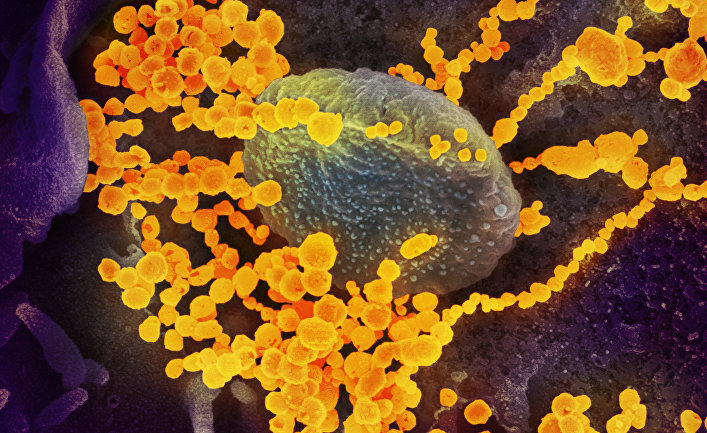

Коронавирус продолжает мутировать, и этот процесс ускоряется за счет многочисленных носителей вируса в разных уголках мира, пишет автор. Она предупреждает: совсем скоро случаи повторного заражения могут стать ужасающей реальностью. Но с чем именно это связано? С мутацией вируса или «странными» сбоями работы иммунной системы? передает UfoSpace.net со ссылкой на inosmi.ru.

Поскольку коронавирус продолжает мутировать, — а этот процесс ускоряется с помощью огромного количества вирусоносителей в разных уголках мира — совсем скоро случаи повторного заражения могут стать ужасающей реальностью. На протяжении большей части 2020 года общепризнанным считался единственный вариант повторного заражения коронавирусом, известным как OG SARS-CoV-2. Не так давно ученые установили несколько случаев, когда выздоровевшие от covid-19 люди заражались новыми вариантами вируса. К настоящему времени эксперты не пришли к единому мнению относительно классификации этих случаев и не могут отличить их от тех случаев, когда иммунная защита человека исчезала.

Рассмотрим, как ведет себя в этой борьбе противная сторона. Хотя коронавирус мутирует медленнее, чем другие респираторные вирусы, он эволюционирует с головокружительной скоростью. Одно-единственное генетическое изменение не делает вирус невидимым для иммунной системы в целом, но последовательные изменения «внешности» способны полностью переделать его в незнакомца. Получается, что последующие случаи инфицирования связаны не столько с плохой памятью организма, сколько с маскировкой вируса — это подобно разнице между ограблением в случае неисправной системы безопасности и преступлением, успех которого объясняется костюмом, в который был одет мошенник. «Организм полагает, что это кто-то совсем другой», — объясняет Брэндон Огбуну (Brandon Ogbunu), эколог и специалист в области вычислительной биологии из Йельского университета. В конце концов, каждый эволюционирующий вирус может настолько измениться, что новое заражение уже будет не реинфицированием, а отдельным случаем, хотя и связанным с первым случаем инфицирования, — сороральным инфицированием или эпи-инфицированием (после-инфицированием).